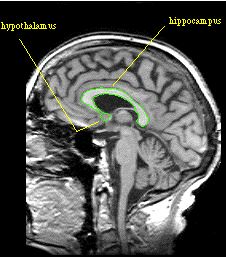

Limbic System and Hypothalamus

Limbic system

- Amygdala

- Hippocampus